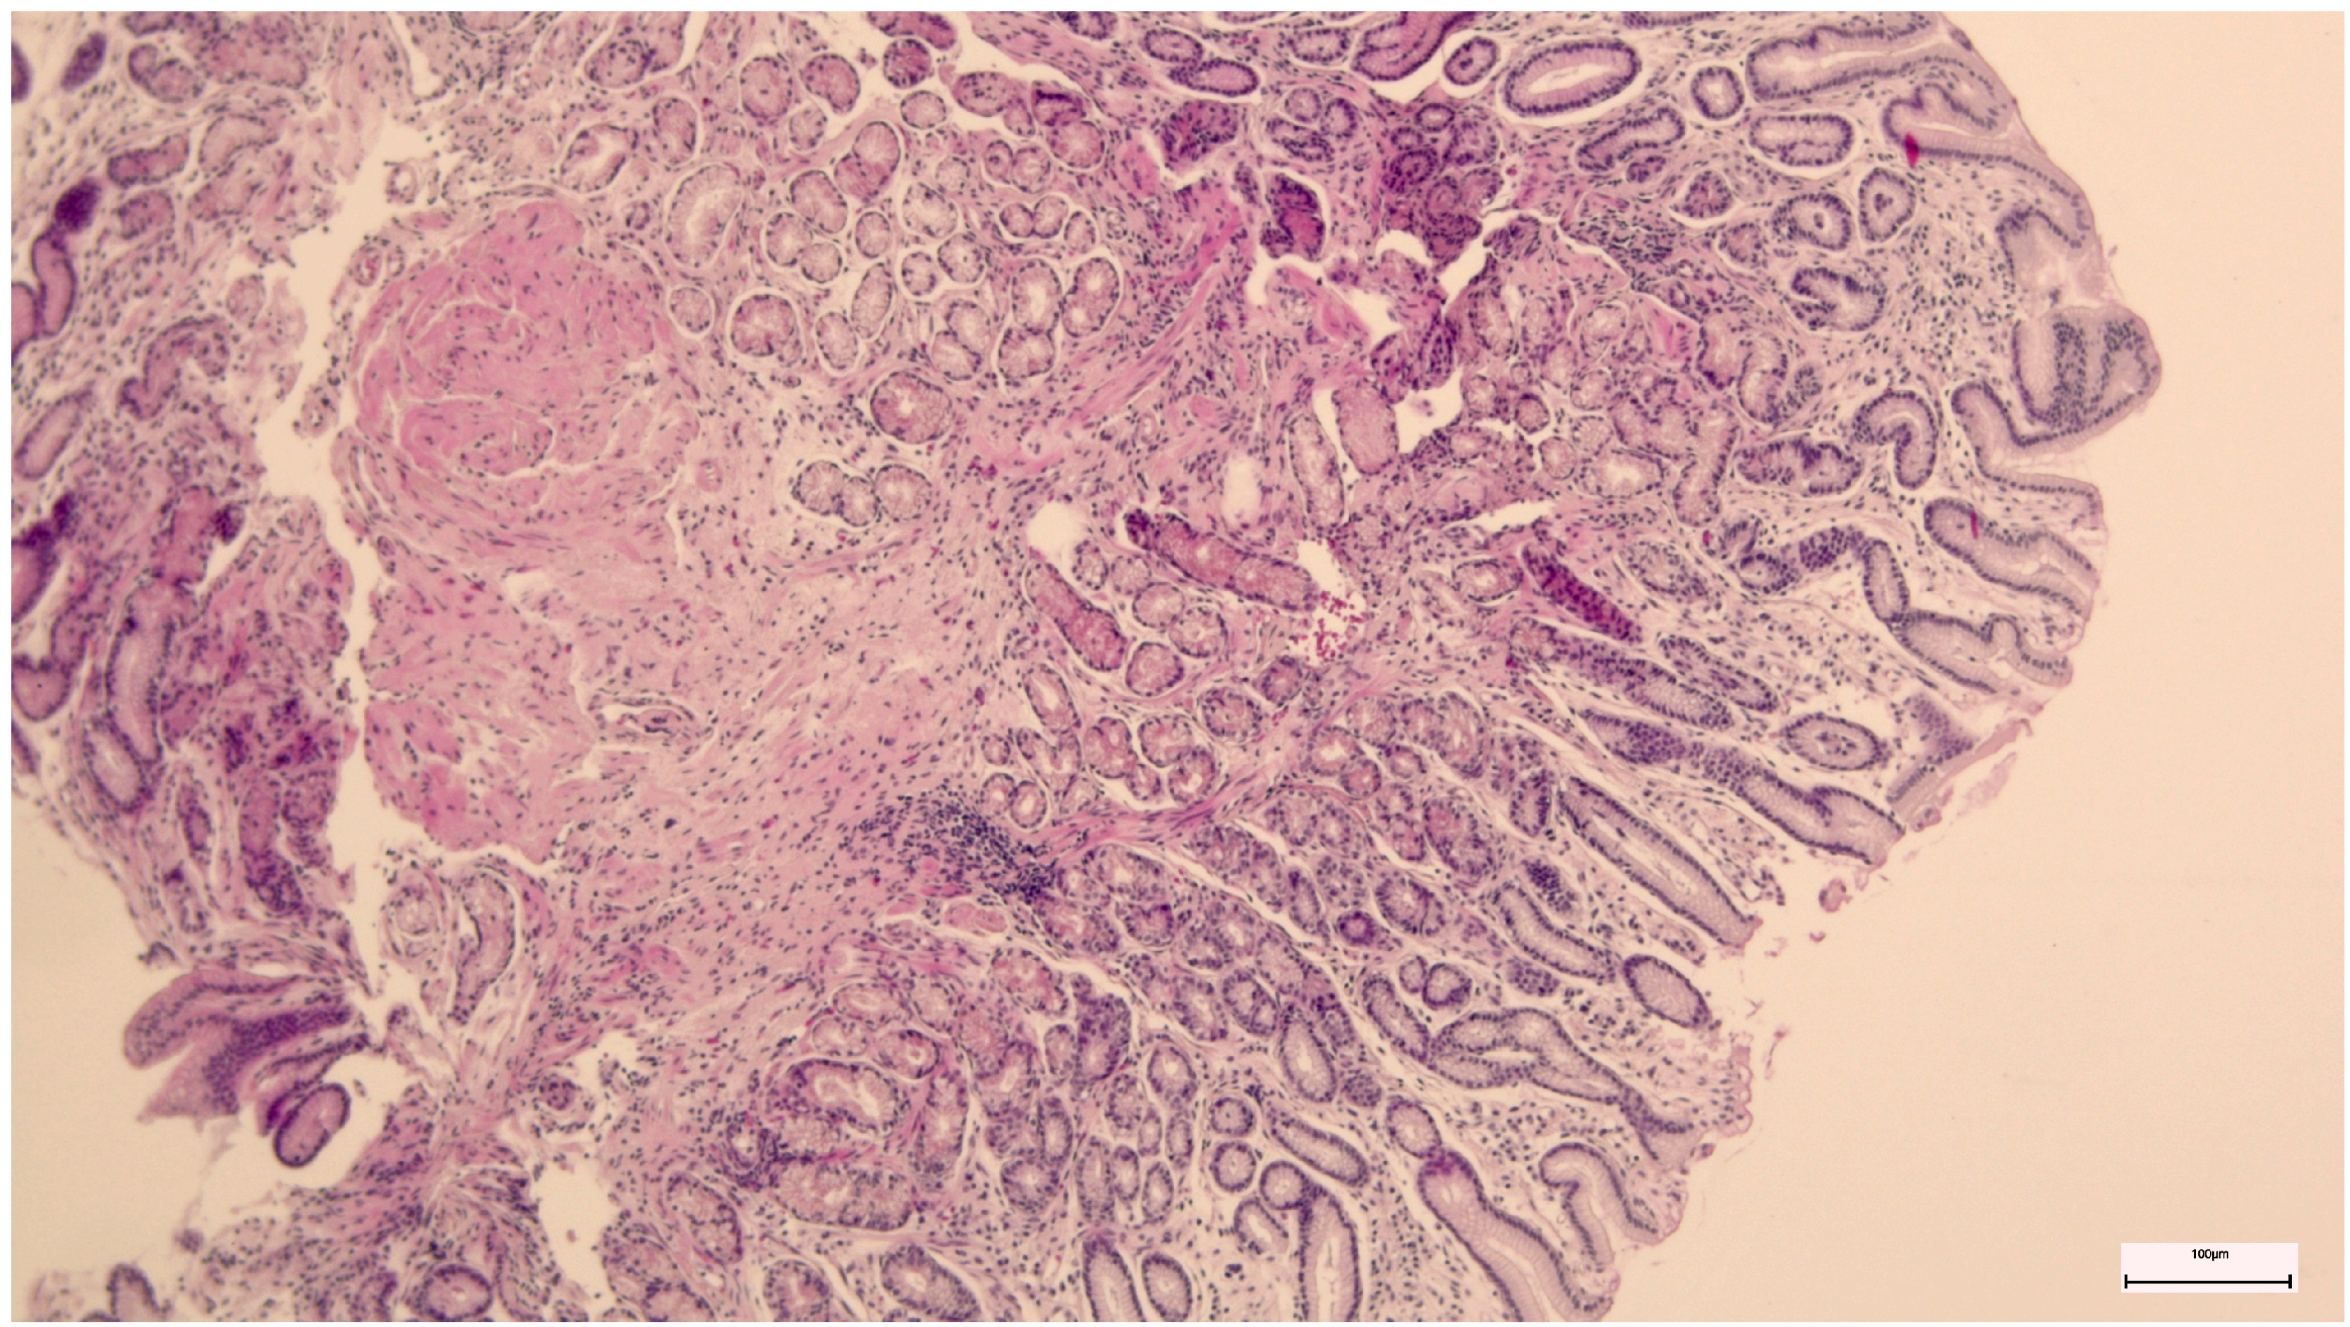

Non-active gastritis was diagnosed if chronic inflammation (represented by the presence of mononuclear and plasma cells within the lamina propria, but not neutrophils) was present. Active gastritis diagnosis was established if acute inflammatory cells were present in corporal and antral mucosa (Figure 3 and Figure 4) [8].

Figure 4. Corporeal active chronic gastritis.